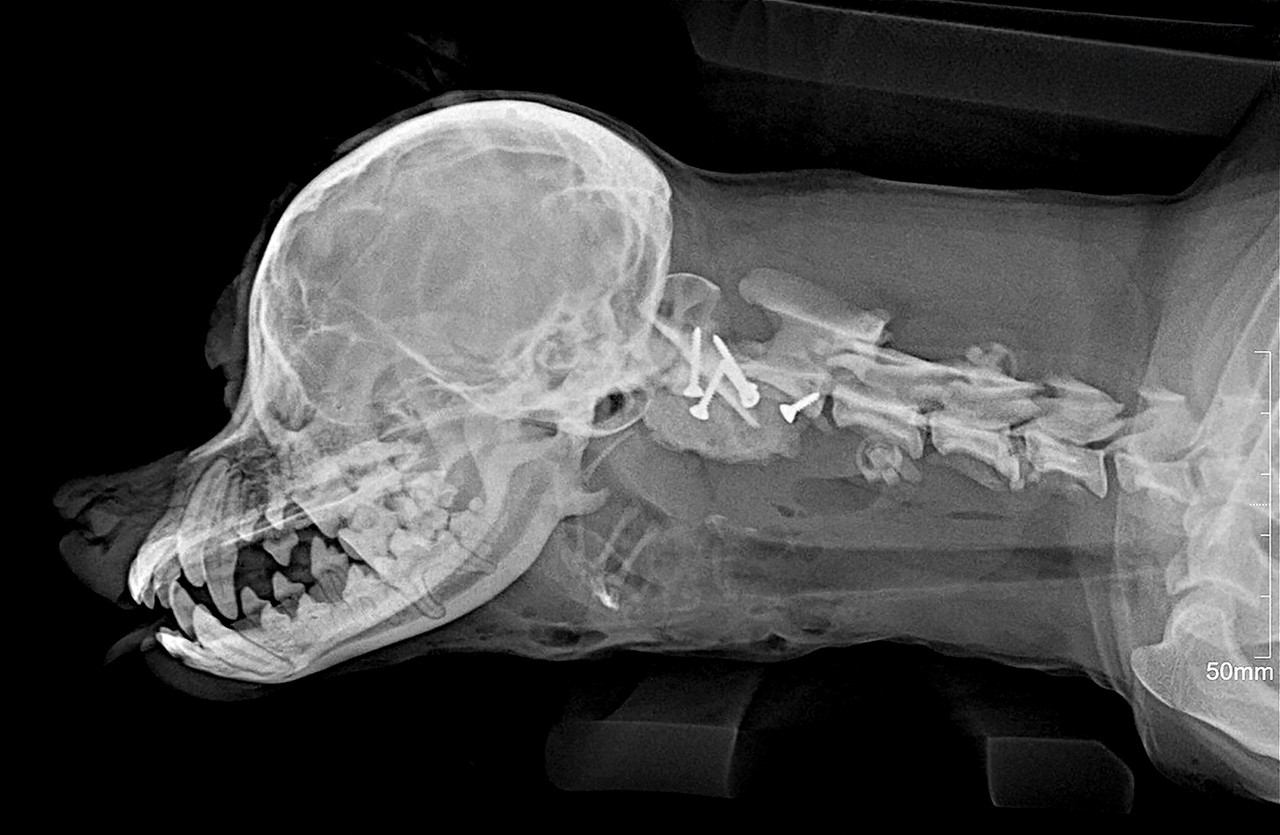

MRI, CT 등 첨단 영상 의료기기를 활용하여 정확하게 진단하고 안전하게 치료하고 있습니다.

1번 경추인 환추와 2번 경추인 축추를 합쳐서 환축추라고 부릅니다.

환축추에 문제가 발생해 불완전한 탈구가 발생하면 척수신경에 영향을 주어 통증 및 사지마비 등이 발생할 수 있습니다.